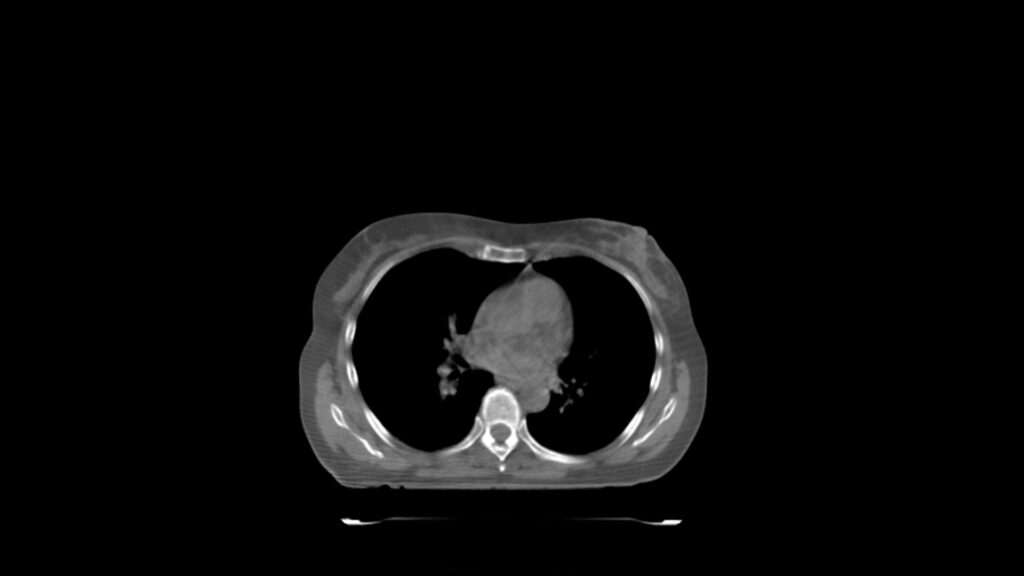

Planning CT Images

Treatment Plan Images

ClearRT® Images

Treatment Delivery Information

Imaging Information

ClearRT®

Protocol

Thorax_Course_Small_44cm

Scan Length

25 cm

KVCT Imaging Time

25 sec

Beam on Time

3.3 min